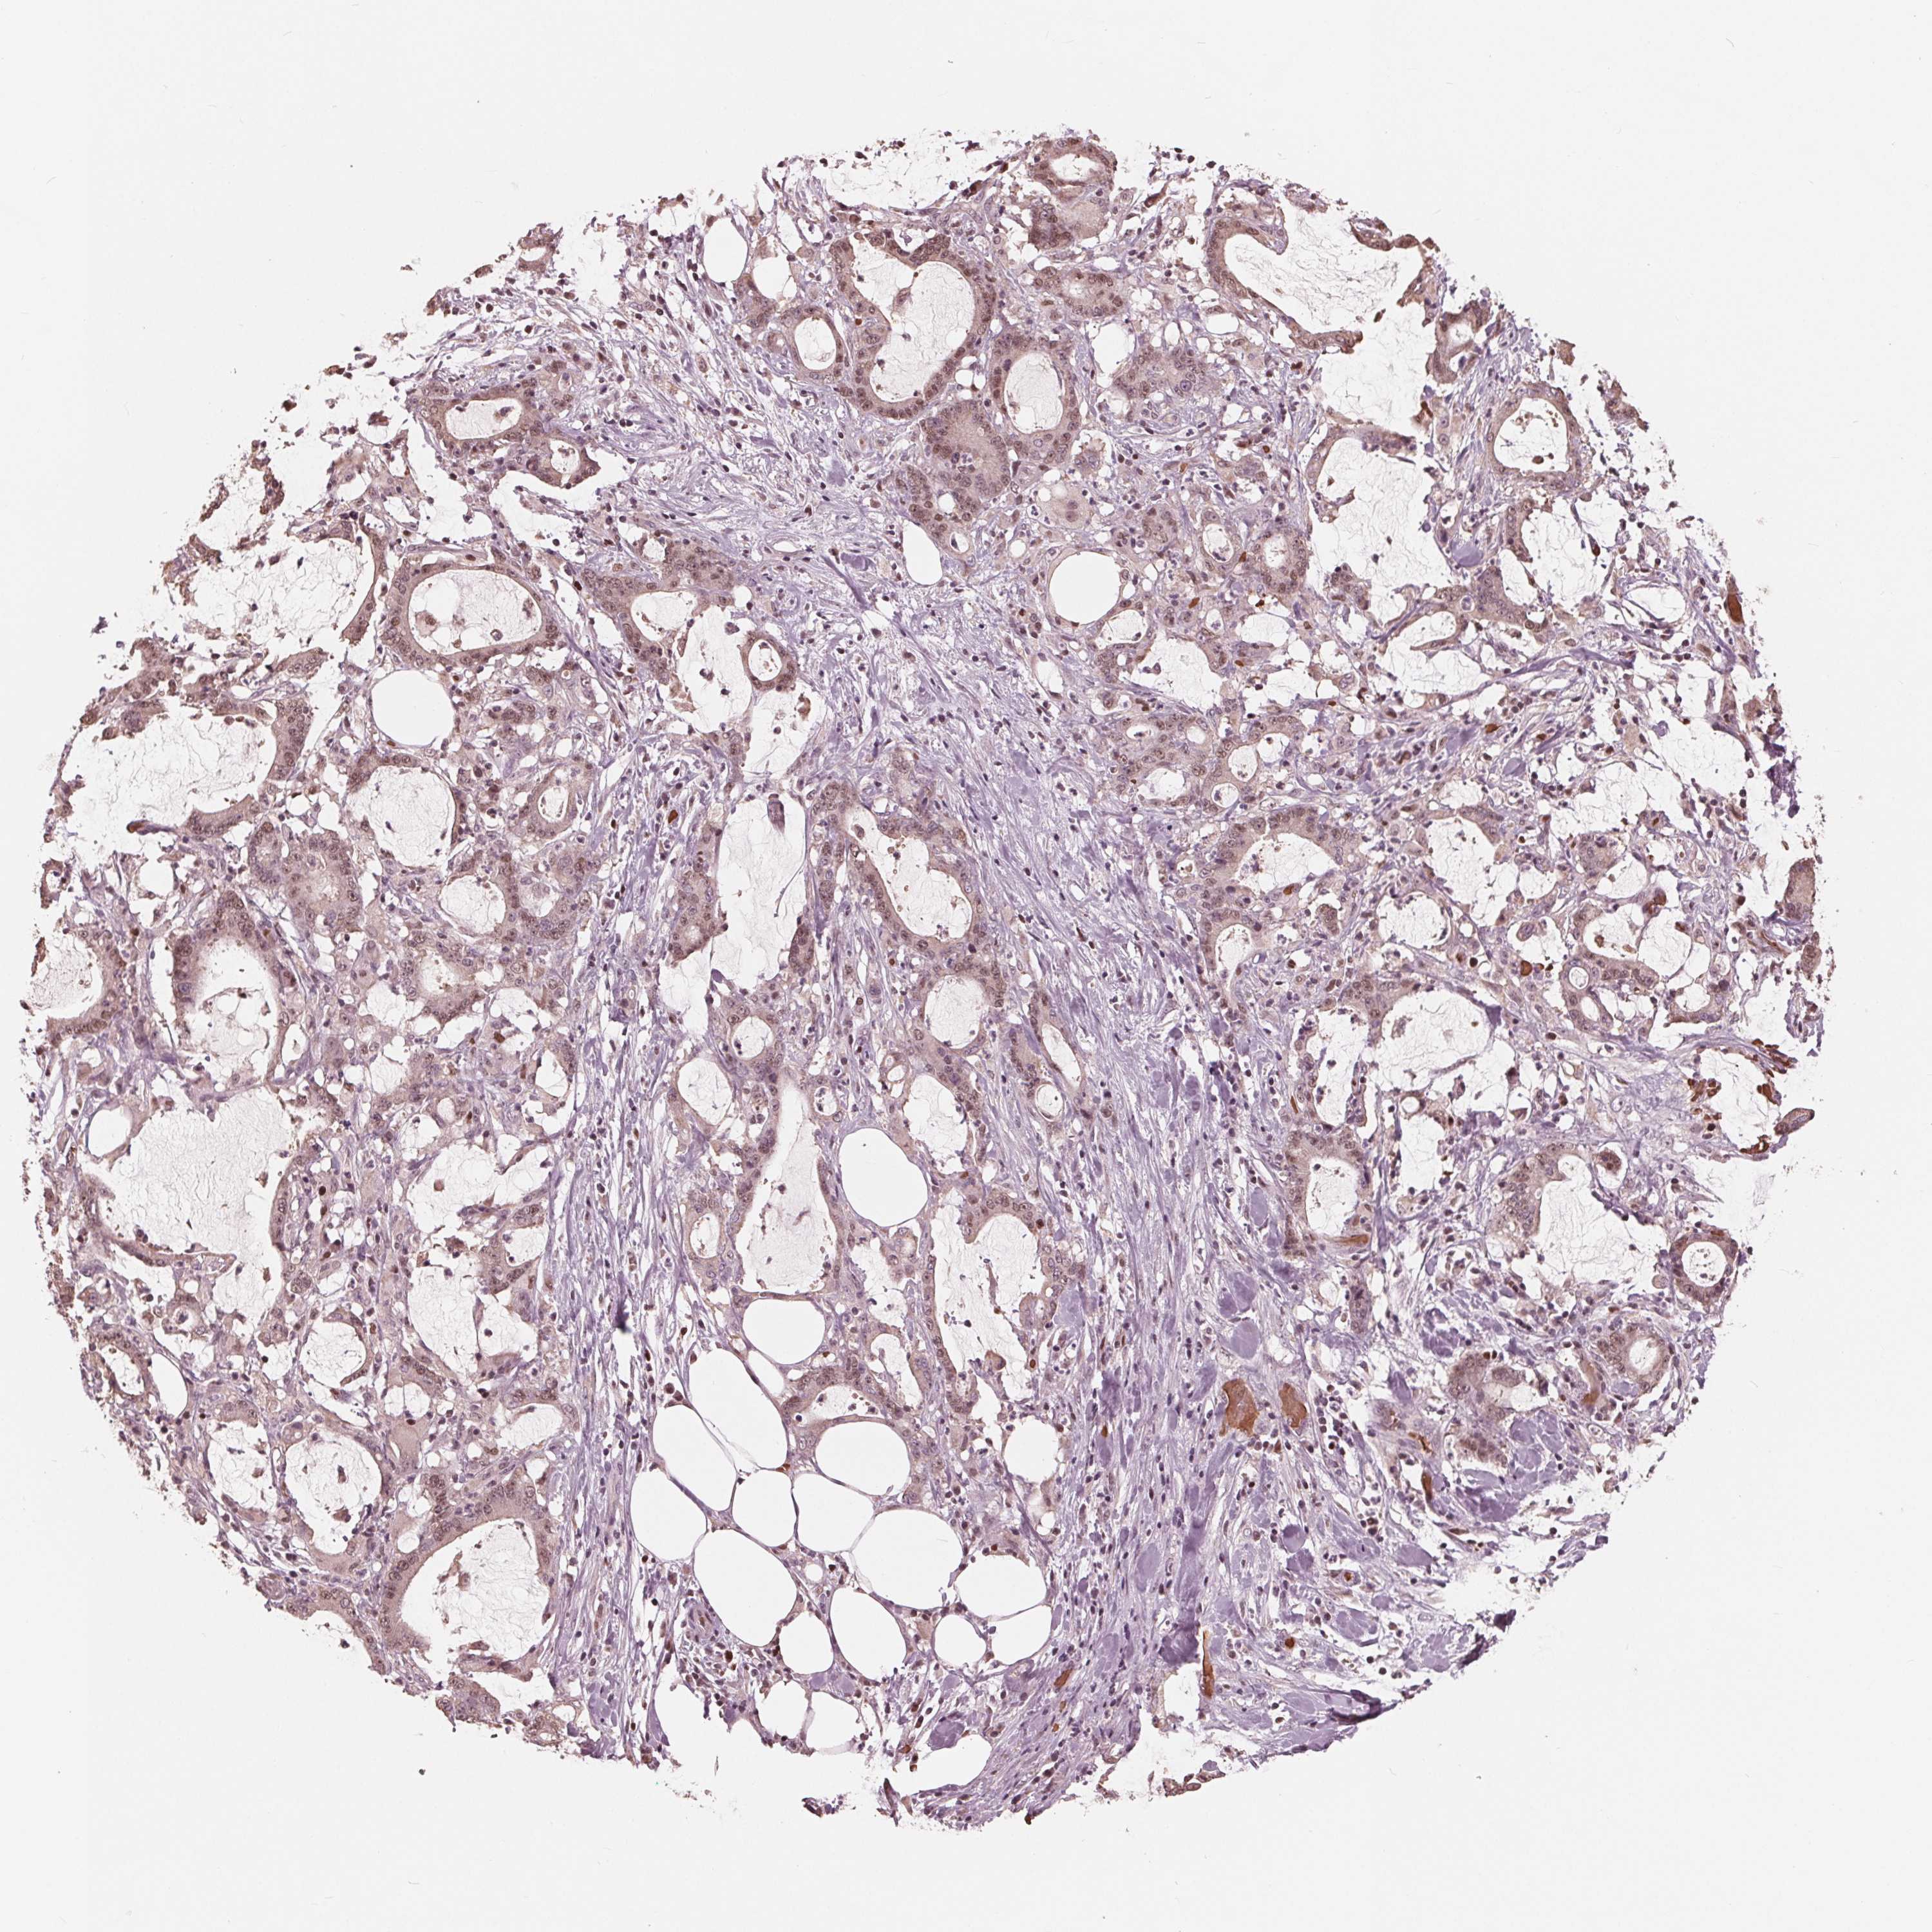

STOMACH CANCER - Protein expressioni

A mouse-over function shows sample information and annotation data. Click on an image to view it in a full screen mode. Samples can be filtered based on level of antibody staining by selecting one or several of the following categories: high, medium, low and not detected. The assay and annotation is described here.

Note that samples used for immunohistochemistry by the Human Protein Atlas do not correspond to samples in the TCGA dataset.

Antibody stainingi

Antibody staining in the annotated cell types in the current human tissue is reported as not detected, low, medium, or high, based on conventional immunohistochemistry profiling in selected tissues. This score is based on the combination of the staining intensity and fraction of stained cells.

Each image is clickable and will lead to virtual microscopy that enables deeper exploration of all samples and also displays staining intensity scores, fraction scores and subcellular localization as well as patient and tissue information for each sample.

Antibody HPA063205

Staining

High

Medium

Low

Not detected

Intensity

Strong

Moderate

Weak

Negative

Quantity

>75%

75%-25%

<25%

None

Location

Nuclear

Cytoplasmic/membranous

Cytoplasmic/membranous,nuclear

Adenocarcinoma, NOS